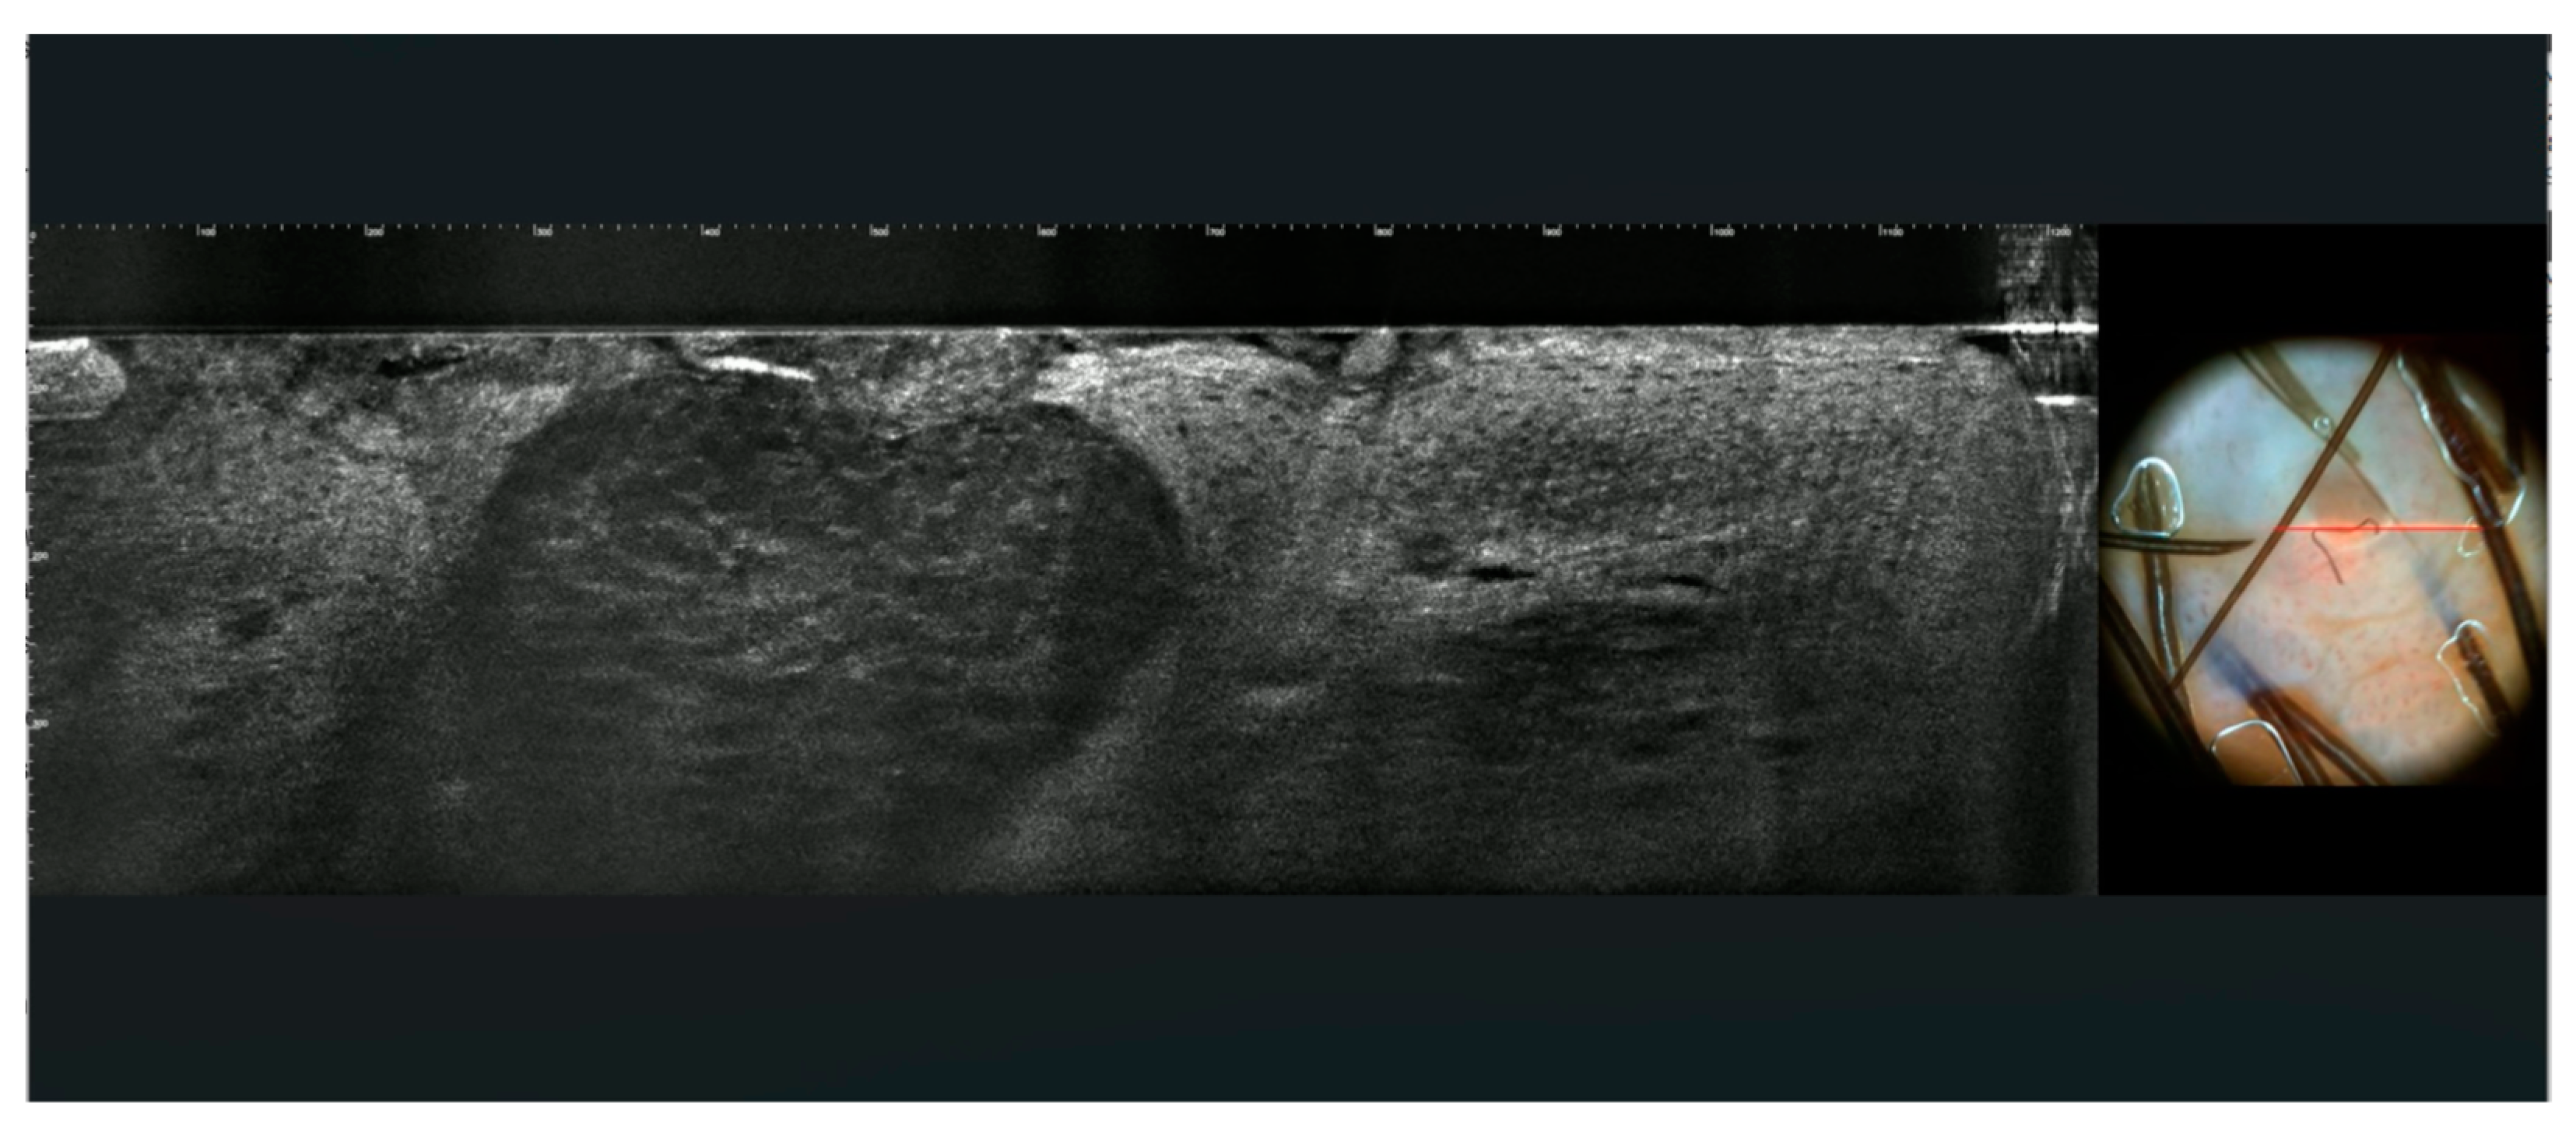

3.2. Images of the Imitators of Genital Warts